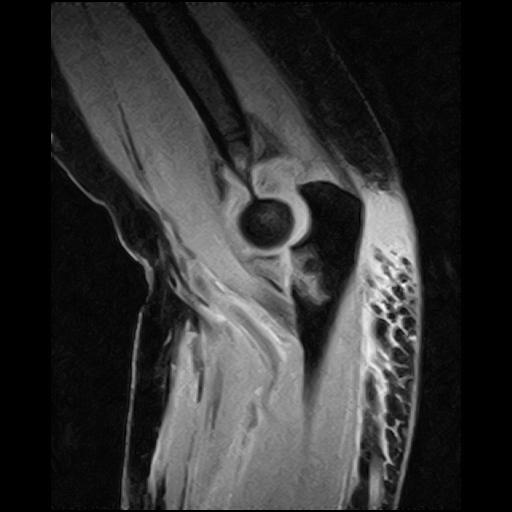

3D T1W GE sequence with spectral fat saturation CHESS enables detailed cartilage visualization.